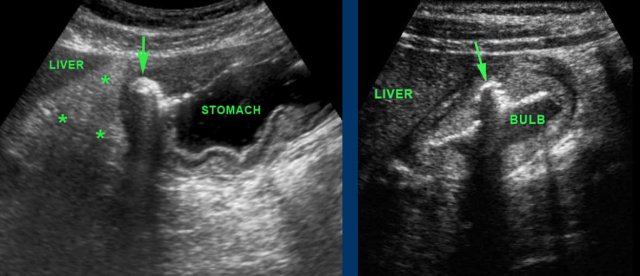

Antrum and duodenal bulb are the parts of the stomach best identified by US.

The pylorus is recognized as a local thickening of the muscularis distally to the antrum.

The wall of the duodenal bulb is thinner than that of the stomach.

Gastric fluid can be used to improve visualization of  the antrum and duodenal area, by turning patients on their right side: air rises to the gastric fundus, and fluid enters antrum and duodenal bulb.

This is especially helpful in adults with  peptic ulcer disease.

The left image shows a gastric ulcer (arrow).

Note the loss of layer structure in the ventral stomach wall and the inflamed fat (asterisks) representing the omentum and mesentery, trying to wall-off the imminent perforation from this deep penetrating gastric ulcer.

The right image shows an ulcer (arrow) in the ventral wall of the fluid-filled duodenal bulb.